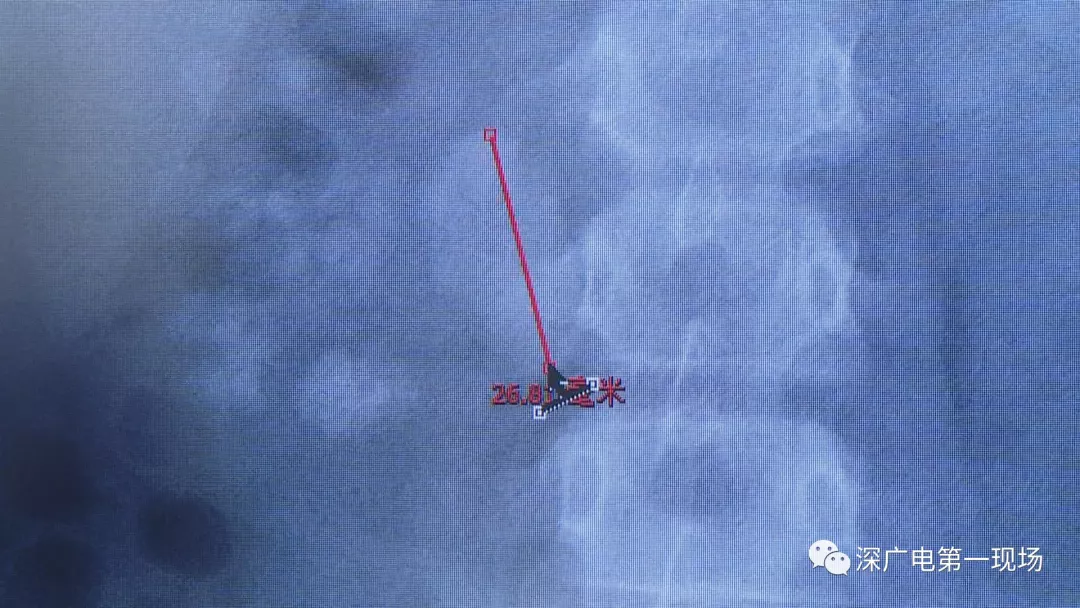

在X光圖像下,醫(yī)生發(fā)現(xiàn)小軒的雙側腎臟都內(nèi)藏乾坤,密密麻麻的分布著大小不等的結石。

醫(yī)生這么解釋:通常情況下,成人只要有0.5厘米大小的結石造成尿路梗阻,就需要及時治療。

小軒這種情況,其中,最大的結石長約2.7厘米,寬約1.7厘米,體積堪比鵪鶉蛋,不但造成了尿路堵塞,還導致了右腎中度積水。